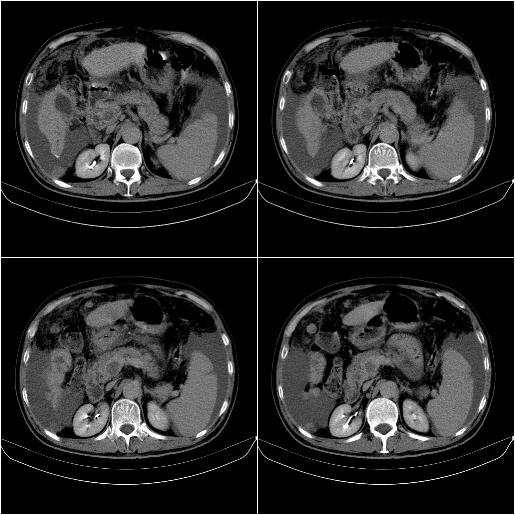

标题: CT21651:M,67Y,肝癌9月,介入术后3月。

m,67y,肝癌9月,介入术后3月。现腹胀、纳差、腹泻。

门静脉有很大的瘤栓,膈肌及膜膜有转移,不用再做了.

情况不好,门静脉癌栓、腹膜转移。

1)肝癌介入治疗术后碘油沉积不良。2)门静脉瘤栓形成,腹膜广泛性转移。3)肝硬化,脾大,腹水。4)慢性胆囊炎。